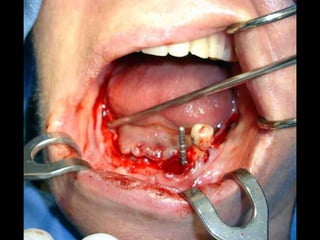

Lingitud de hueso

Disponible 20 mm.

Implante en posición

Dejamos el implante sepultado por 4 meses previos al inicio del procedimiento

Protésico.

Dejamos el implantesepultado por 4 meses previos al inicio del procedimiento Protésico.

• Los implantesdeben dejarse sin carga unLos implantes deben dejarse sin carga un promedio aproximado de cuatro meses,promedio aproximado de cuatro meses, después de los cuales se inicia el trabajodespués de los cuales se inicia el trabajo protésico.protésico. • Cuidados postoperatorios: Analgésicos,Cuidados postoperatorios: Analgésicos, antibióticos y antiinflamatorios, hielo local lasantibióticos y antiinflamatorios, hielo local las primeras horas y dieta licuada los 3 primerosprimeras horas y dieta licuada los 3 primeros días.días.